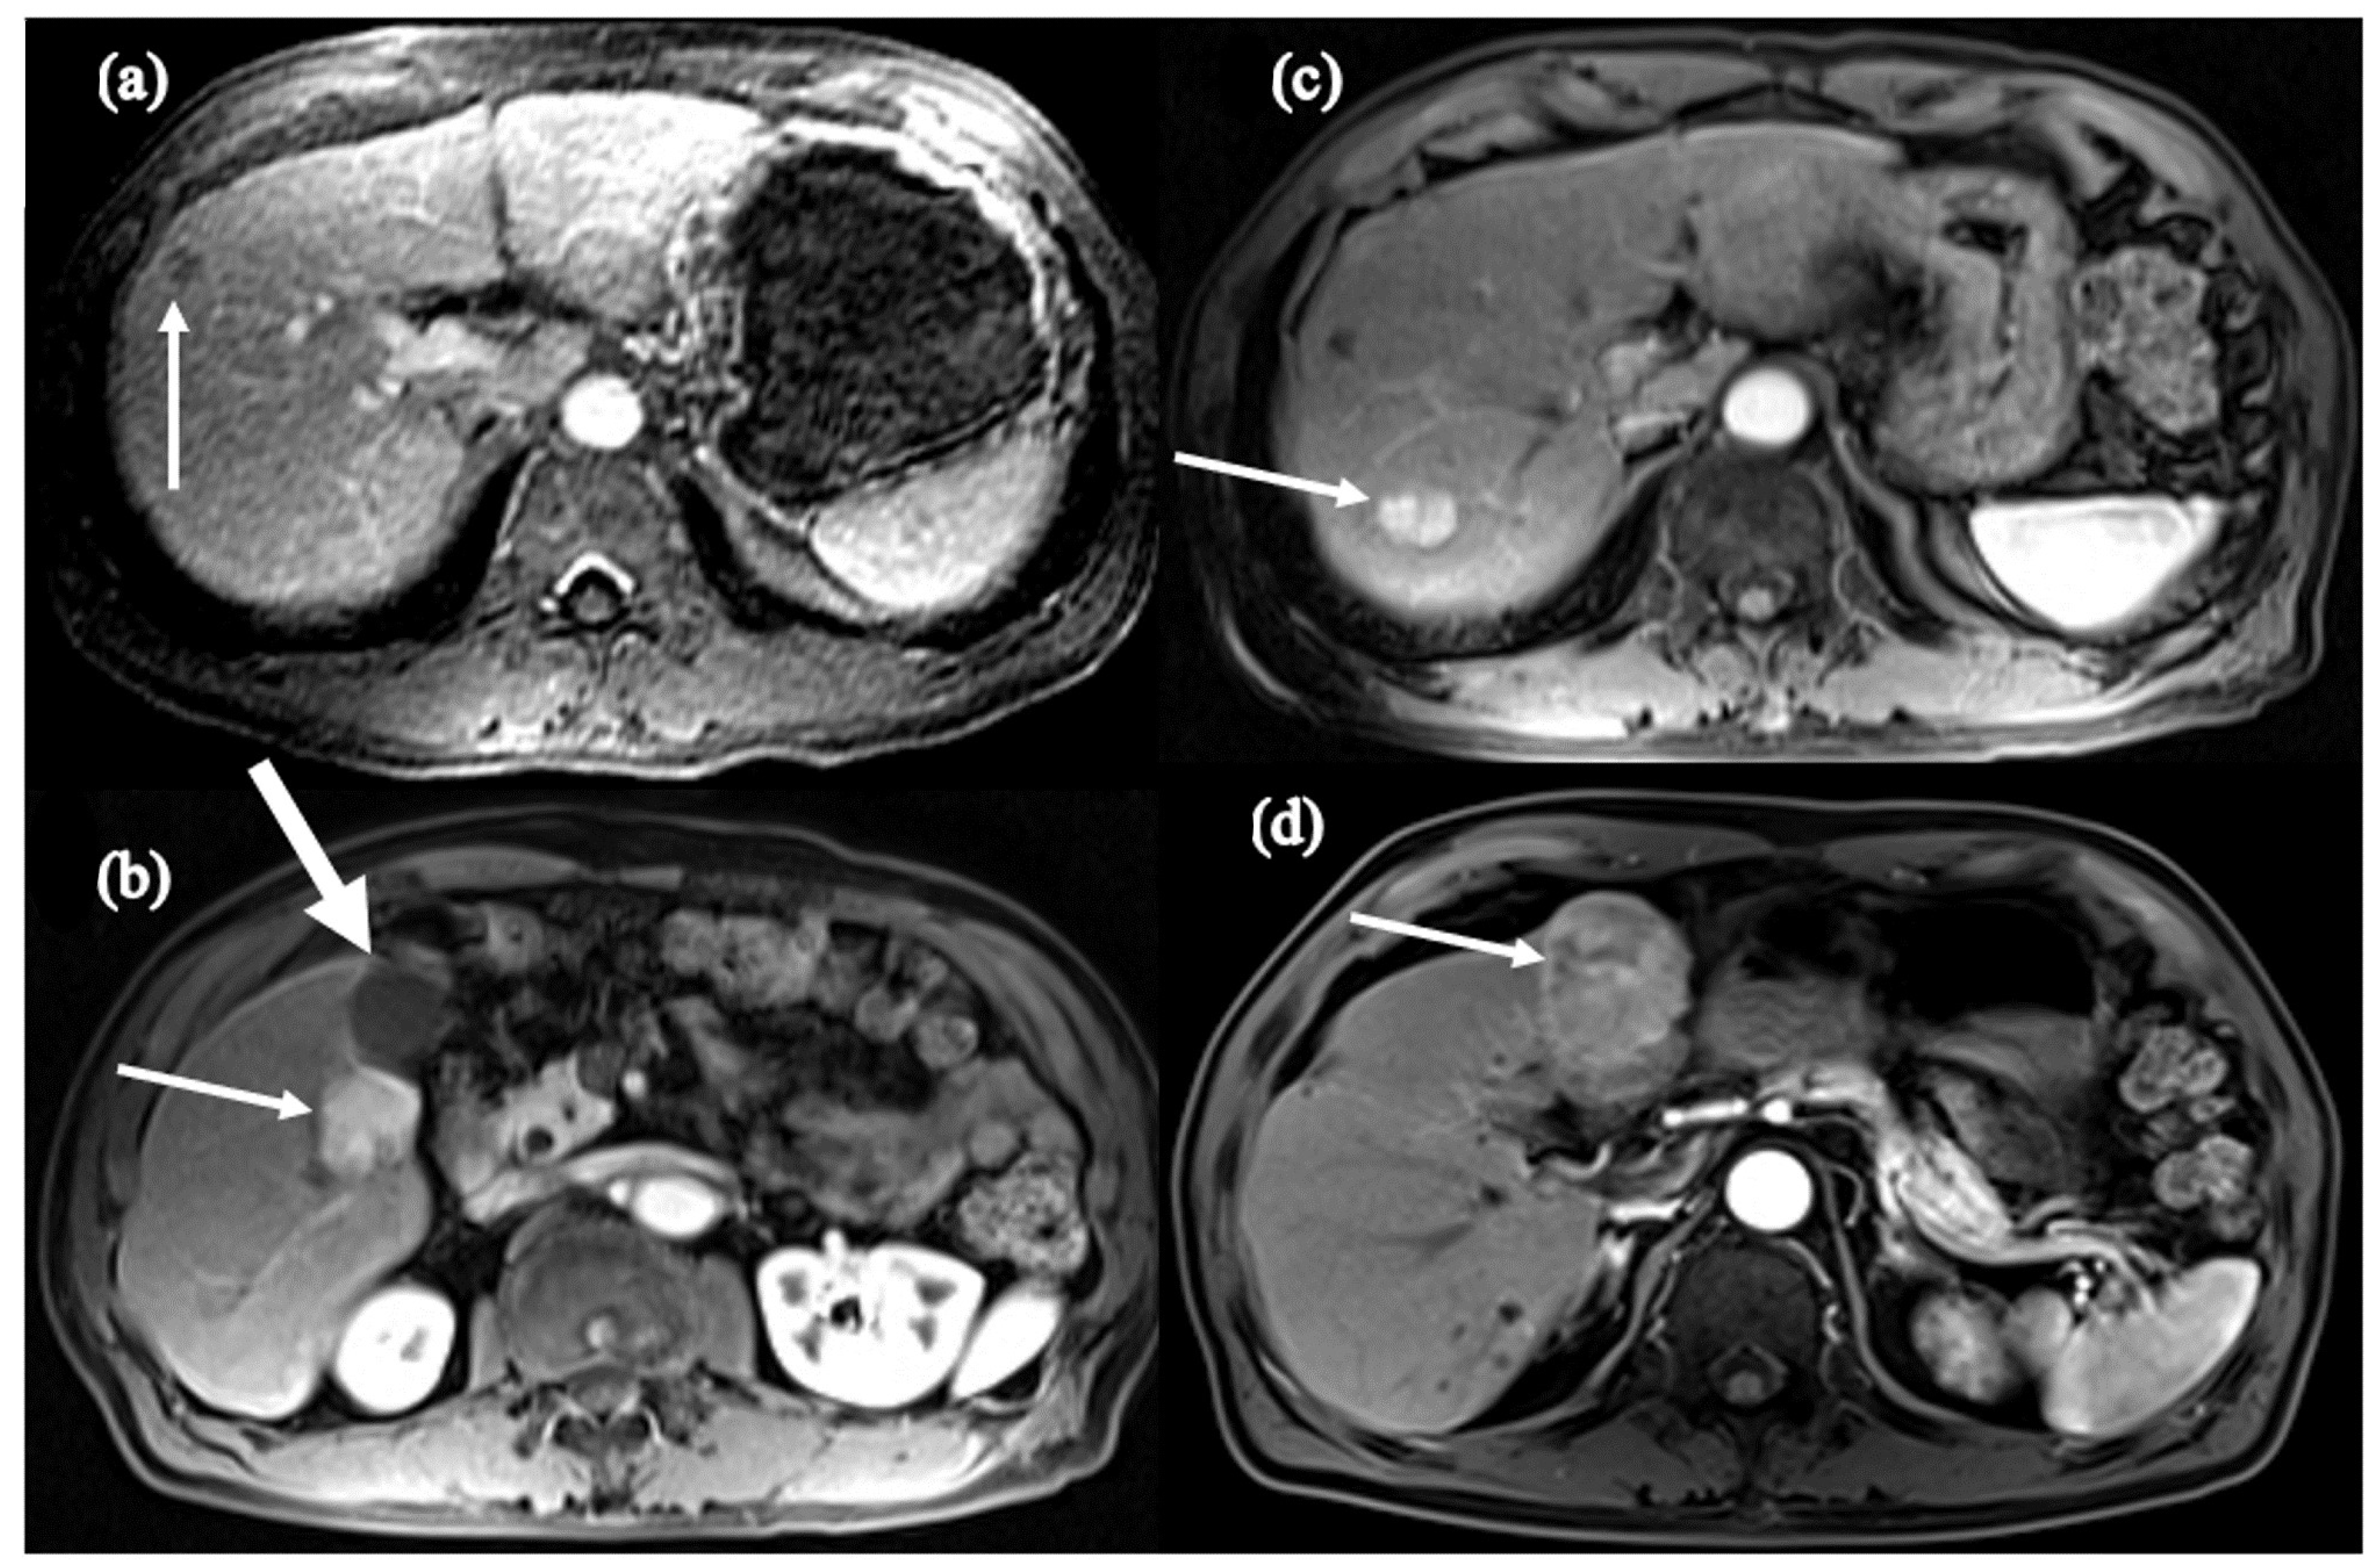

- Shinn, B.J.; Martin, A.; Coben, R.M.; Conn, M.I.; Prieto, J.; Kroop, H.; DiMarino, A.J.; Hann, H.W. Persistent risk for new, subsequent new and recurrent hepatocellular carcinoma despite successful anti-hepatitis B virus therapy and tumor ablation: The need for hepatitis B virus cure. World J. Hepatol. 2019, 11, 65–73. [Google Scholar] [CrossRef] [PubMed]

- Boortalary, T.; Shinn, B.; Coben, R.M.; Conn, M.I.; Prieto, J.; Kroop, H.; Dimarino, A.; Hann, H. Are We Close to Achieving a HBV Cure? Risk for Hepatocellular Carcinoma Persists Despite Long-term HBV Suppression: An Update on Our Experience. Arch. Gastroenterol. Res. 2020, 1, 105–110. [Google Scholar]